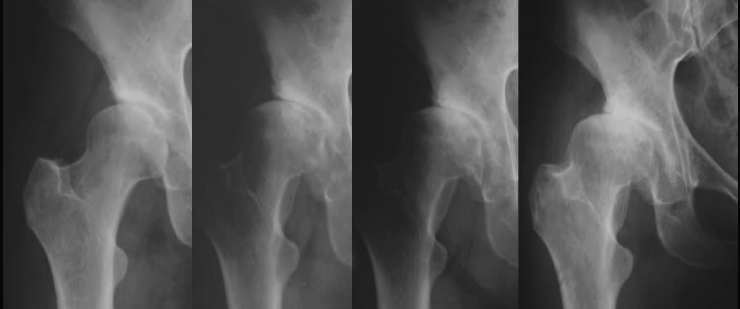

Left hip severe dysplasia with coxa vara and magna treated with PAO and RNL

Left hip severe dysplasia with coxa vara and magna treated with PAO and RNL.